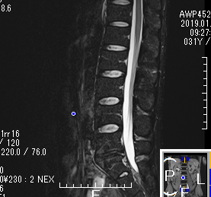

椎間板ヘルニア

2年前から腰痛を感じ少しずつ悪化、1年前に整形外科を受診し、MRI検査で椎間板ヘルニアと診断される。